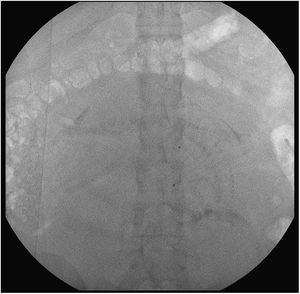

Guiada por ecografía, se realizó punción de la arteria femoral común derecha con una aguja de 19 G. A través de la misma se pasó una guía teflonada en J de 0,035 pulgadas, que sirvió de soporte para colocar el set introductor de 23cm de longitud y 6 F de diámetro. Dado que el introductor de 23cm garantiza con un 95% de probabilidad la localización en la aorta infrarrenal de su extremo distal6, se realizó una sola adquisición de escopia para comprobar dicha posición (fig. 3). No fue necesario el uso de contraste por vía intravenosa. Posteriormente, se procedió a introducir el balón REBOA por el introductor hasta hacer coincidir la marca de color negro con la válvula (fig. 4). Se comprobó su correcto funcionamiento tras verificar un aumento de la presión arterial sistólica de la paciente una vez hinchado el balón con 8ml de suero fisiológico. Posteriormente, se dejó deshinchando, conectado a una llave de 3 pasos, preparado para ser usado durante la cirugía que transcurriría a continuación.

En los 6 casos realizados, los balones aórticos fueron útiles para detener el sangrado y favorecer una intervención más cómoda y rápida, aportando mejor visibilidad del campo quirúrgico. No hubo complicaciones derivadas del acceso femoral. Aunque se obtuvo una imagen de escopia de segundos de duración y baja dosis de radiación para asegurarse de la localización del balón, esta podría ser prescindible por las características del kit REBOA, el cual garantiza, con un 95% de probabilidad, que si el balón es introducido hasta la marca negra (como se muestra en la fig. 4), este va a situarse en la aorta infrarrenal.